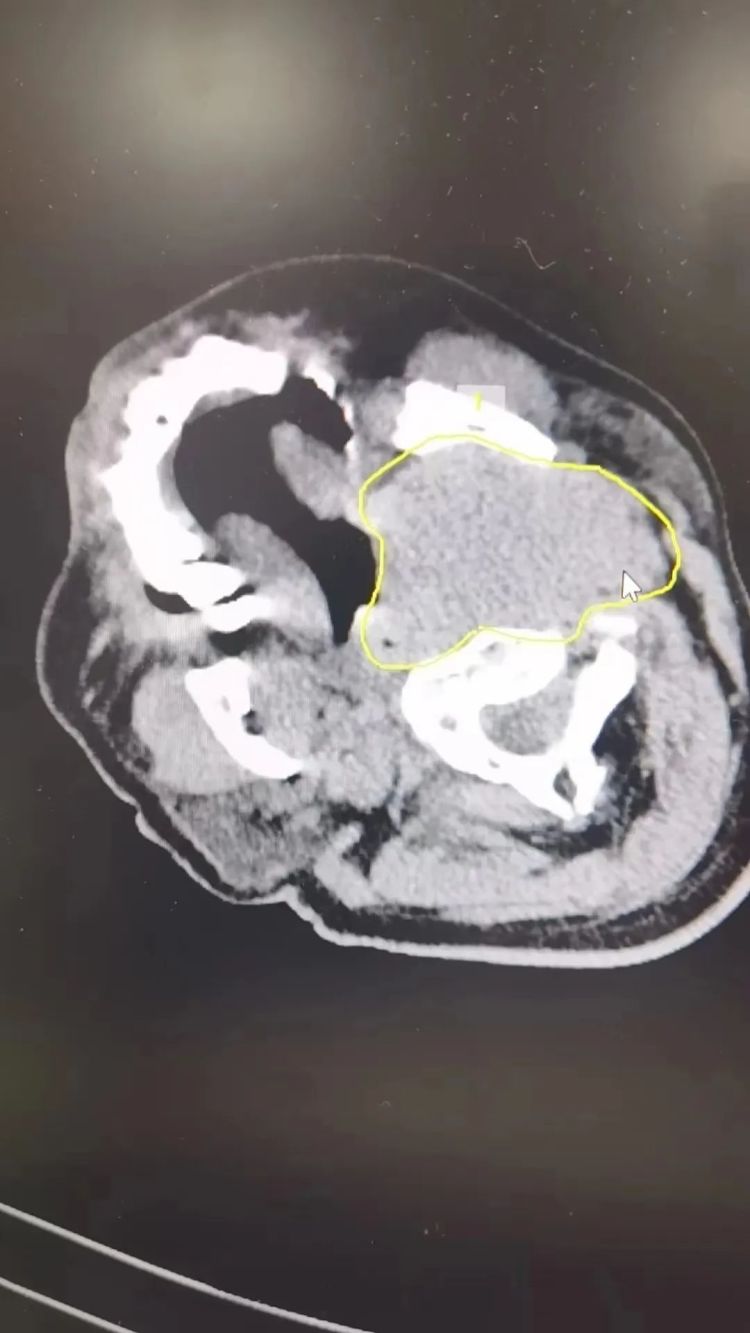

很快,雷先生在医院接受了头颅CT、MRI等一系列检查,医生发现其有脑积水,此外左侧颈静脉窦处有一个4x6cm的病灶。

(下图黄圈处)

接诊的福州市第一总医院肿瘤整合科骆华春医生初步诊断,雷先生反复晕厥休克,就是这个鸡蛋大的病灶,压迫颈静脉窦引起的,查到了病灶,明确诊断还没结束。这个病灶是好是坏还不清楚,骆华春马上为雷先生进行病理穿刺,并联系医院病理科黄玉钿主任,最终通过24小时快速病理诊断,明确病理结果为“恶性弥漫大B淋巴瘤” 。